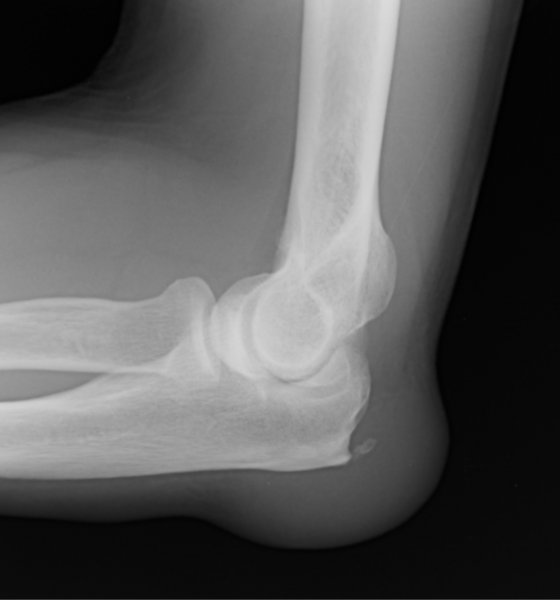

Examination of the joint shows a soft lump on the back of the elbow. There may be redness and warmth if there is an underlying infection. An X-ray may be performed to look for bone spurs and to assess the joint surfaces. Blood tests may be arranged to exclude gout.